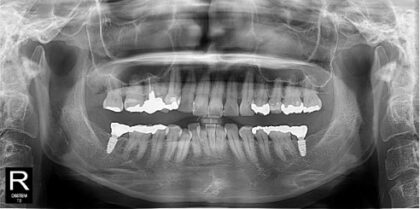

オールオン4 レスキュー症例

| 主訴 | 他院にて8~9年前にインプラントの手術を行ったがその後閉院してしまった。現在仮歯の状態なため治療を終わらせたい。 |

| 治療内容 |

仮歯・土台・ねじの破折など様々な問題がありました。全て除去し新しい土台を入れて、ジルコニア製の上部構造を装着しました。 |